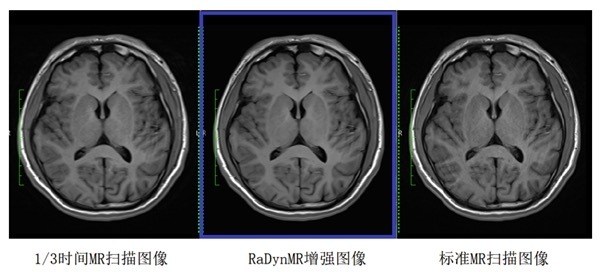

RaDynMR是影动医疗旗下的一款专为 MRI 临床影像而开发的,基于影动医疗的深度学习和图像重建增强技术,通过降低图像噪声和提高图像分辨率的算法,在保证诊断级图像质量的同时,显著提升了 MRI 的扫描速度,提高病人通量30%~50%。

RaDynMR加速扫描增强对比图